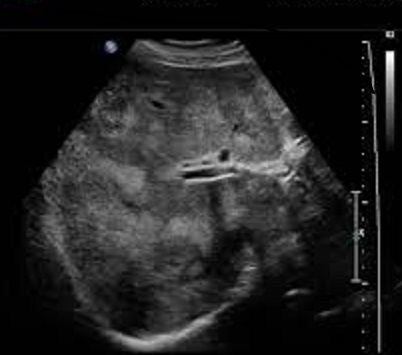

Image echographique du

carcinome hepatocellulaire : Aspect lesionaire du HCC

est une masse hyperechogene , hypoechogene ou mixte , unique

ou multiple a contour net irregulier ou mal de definissable

. Au debut , le forme plus souvent est un infiltrant a

isoechogene ,et puis sous forme nodulaire de petite

taille est hypoechogene et si en forme nodulaire de grand

taille c'est hyperechogen avec des zones necrotiques

hypoechogenes . Le " Rim sign " ou signe de "Bending sign "

le plus souvent en voyait dans HCC , ce qui en n'a pas presente

dans abces du foie . De HCC a grand taille , aspect

echographique est un masse hyperechogene multinodulaire a

contour maldefinie avec centre necrotique hypoechogene de

contenant des bougeons . Image echogaphique de thrombus de

veine porte

Image echographique de

metastase du foie : Aspect lesionaire est multiple

en nodulaire iso echogen avec contour

hypoechogen ( Bull's eye sign) |

Signe de "Bull

eye sign" des metastases du foie . Image

echographique du foie |